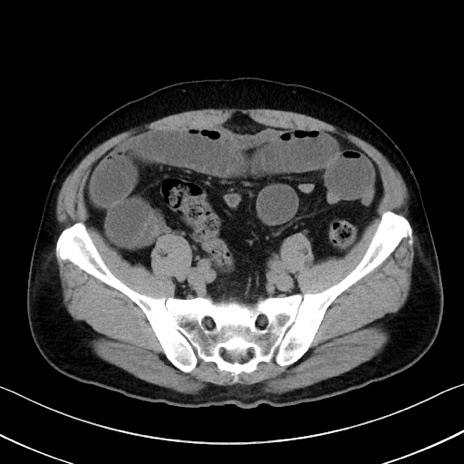

症例35(横断像)

【症例】70歳代 男性

【主訴】腹部膨満、嘔吐

【現病歴】昨日より腹部膨満感出現。本日増悪し、仙痛出現。嘔吐あり、受診。

【既往歴】糖尿病、胆摘後

【身体所見】BP 149/80mmHg、HR 74/min、BT 35.9℃、腹部:膨満、軟、圧痛なし。腸雑音減弱あり。上腹部正中切開瘢痕あり。

【データ】WBC 13500、CRP 1.72